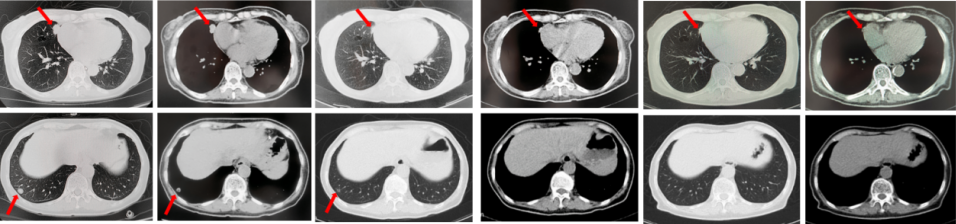

2022年7月至2022年11月行贝伐珠单抗联合培美曲塞/顺铂方案治疗6周期,2周期后评效PR,4周期后评效SD-(如图1)。第6周期治疗结束后患者自行终止治疗。

图1:由左至右分别展示基线(A.)及一线治疗后改变(B.和C.)。红色箭头指示病灶位置,由上至下分别为右肺肿物、右侧胸膜转移病灶及胸腔积液、左侧胸膜转移病灶、多发纵隔淋巴结肿大。

2023年3月患者因咳嗽伴胸闷复查出现全面PD。2023年3月-2023年4月重启原方案贝伐珠单抗联合培美曲塞/顺铂治疗2周期。2023年5月复查评效PD。行左锁骨上淋巴结穿刺,病理回报:左锁骨上见异型细胞,考虑为癌可能性大。组织NGS基因检测:MET基因扩增(变异倍数)2.0倍,TP53错义突变,PD-L1(22C3):TPS 75%。2023年5月-2023年8月改行替雷利珠单抗联合紫杉醇脂质体治疗4周期,2周期后评效SD。(如图2)

图2:A.代表一线治疗停药后病情进展,右肺上叶肿物、右侧胸膜转移灶及纵隔淋巴结较前增大、增多,右侧胸腔积液较前增多;B.原方案重启后复查评效右肺上叶肿物及纵隔淋巴结较前略饱满,右侧胸腔积液较前明显增多;C.更改二线治疗方案后整体病灶较前无显著变化。